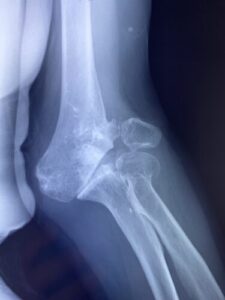

春日部市市民活動センター(肘関節脱臼)

【整骨研究会「賜恩」での症例発表】

小児上腕骨外顆回転骨折の1症例について

肘関節前方脱臼の1症例について